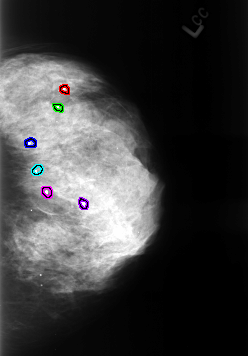

B_3248_1.LEFT_CC

FILE: B_3248_1.LEFT_MLO.OVERLAY

TOTAL_ABNORMALITIES 6

FILE: B_3248_1.LEFT_CC.OVERLAY

FILE: B_3248_1.RIGHT_CC.OVERLAY